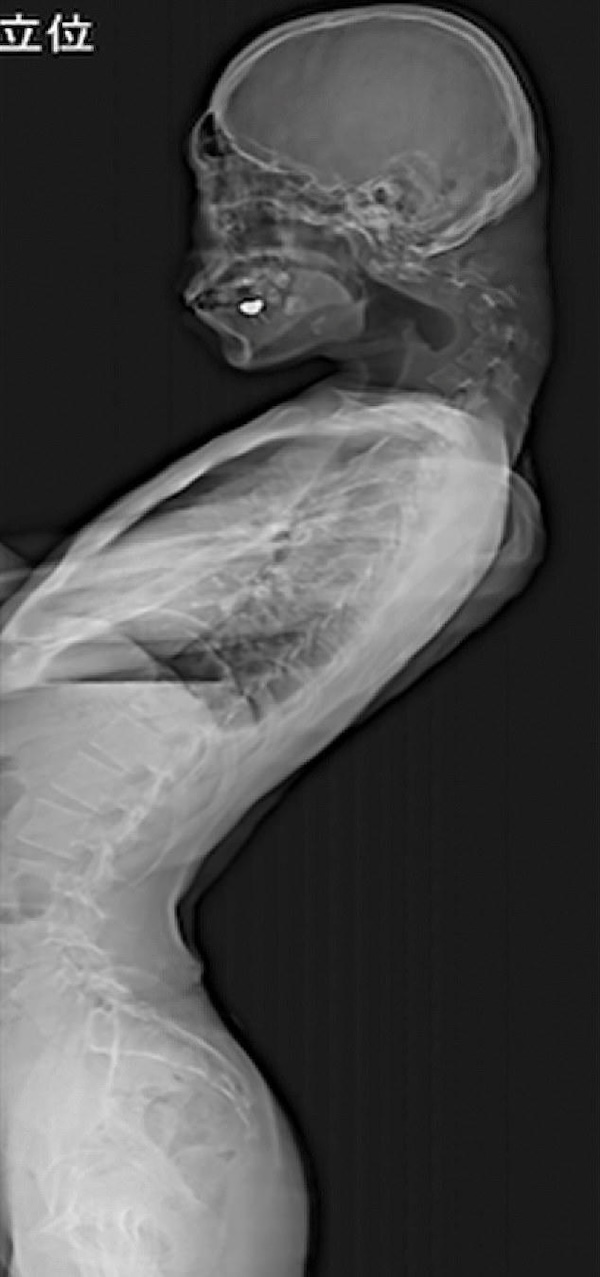

25-Year-Old Develops Permanent Neck Bend From Staring at His Phone

This prolonged posture didn’t just earn him high scores. He developed a pronounced bulge at the back of his neck, rendering him unable to lift his head, and was diagnosed with Dropped Head Syndrome.